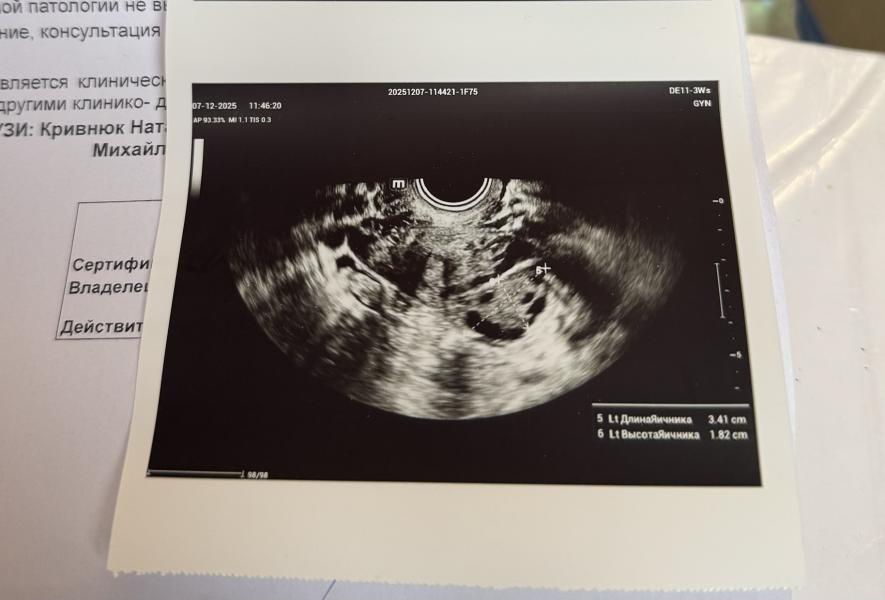

Была на узи, что имеем. 20дц (5 дпо) овуляция была слева, как я и чувствовала. Эндометрий 10,6мм, а вот ЖТ совсем расстроило - 14мм всего… во вторую в 5 недель ЖТ было 17мм, в третью 25мм. Значит можно не надеяться уже на этот цикл. Ну ничего, зато встречу Новый год со своим любимым шампанским 🥂

(На фотке с узи улыбается левый яичник, в котором была О 😆)